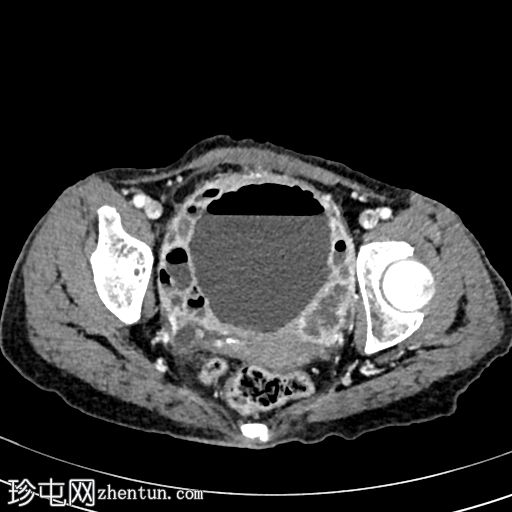

CT

轴位

非增强

1.jpg

可见膀胱壁不规则弥漫性明显增厚,伴壁内气体,符合气肿性膀胱炎的影像学表现。

可见双侧膀胱输尿管连接处闭塞,导致双侧肾盂输尿管积水。

右肾中度肾积水,肾实质厚度正常;左肾重度肾积水,肾实质厚度减少。